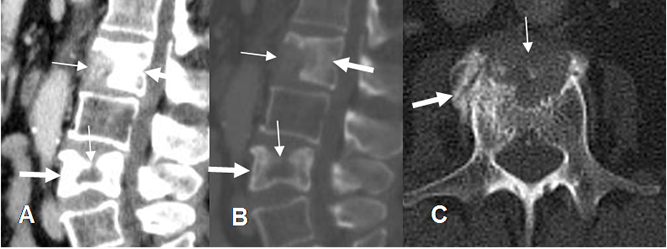

Fig 227. Metástasis mixtas.

A: TAC reconstrucción sagital en ventana de tejido, B: TAC reconstrucción sagital en ventana ósea y C: TAC axial Múltiples lesiones líticas (Flechas delgadas) y blásticas (Flechas gruesas), por neoplasia de mama.